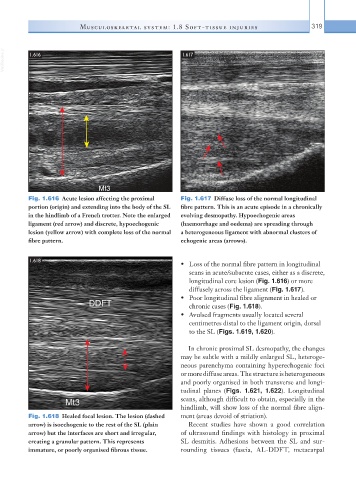

Fig. 1.618  Healed focal lesion. The lesion (dashed   ment (areas devoid of striation).

arrow) is isoechogenic to the rest of the SL (plain   Recent studies have shown a good correlation

arrow) but the interfaces are short and irregular,   of ultrasound findings with histology in proximal

creating a granular pattern. This represents   SL desmitis. Adhesions between the SL and sur-

immature, or poorly organised fibrous tissue.  rounding tissues (fascia, AL-DDFT, metacarpal

• Poor longitudinal fibre alignment in healed or

chronic cases (Fig. 1.618).